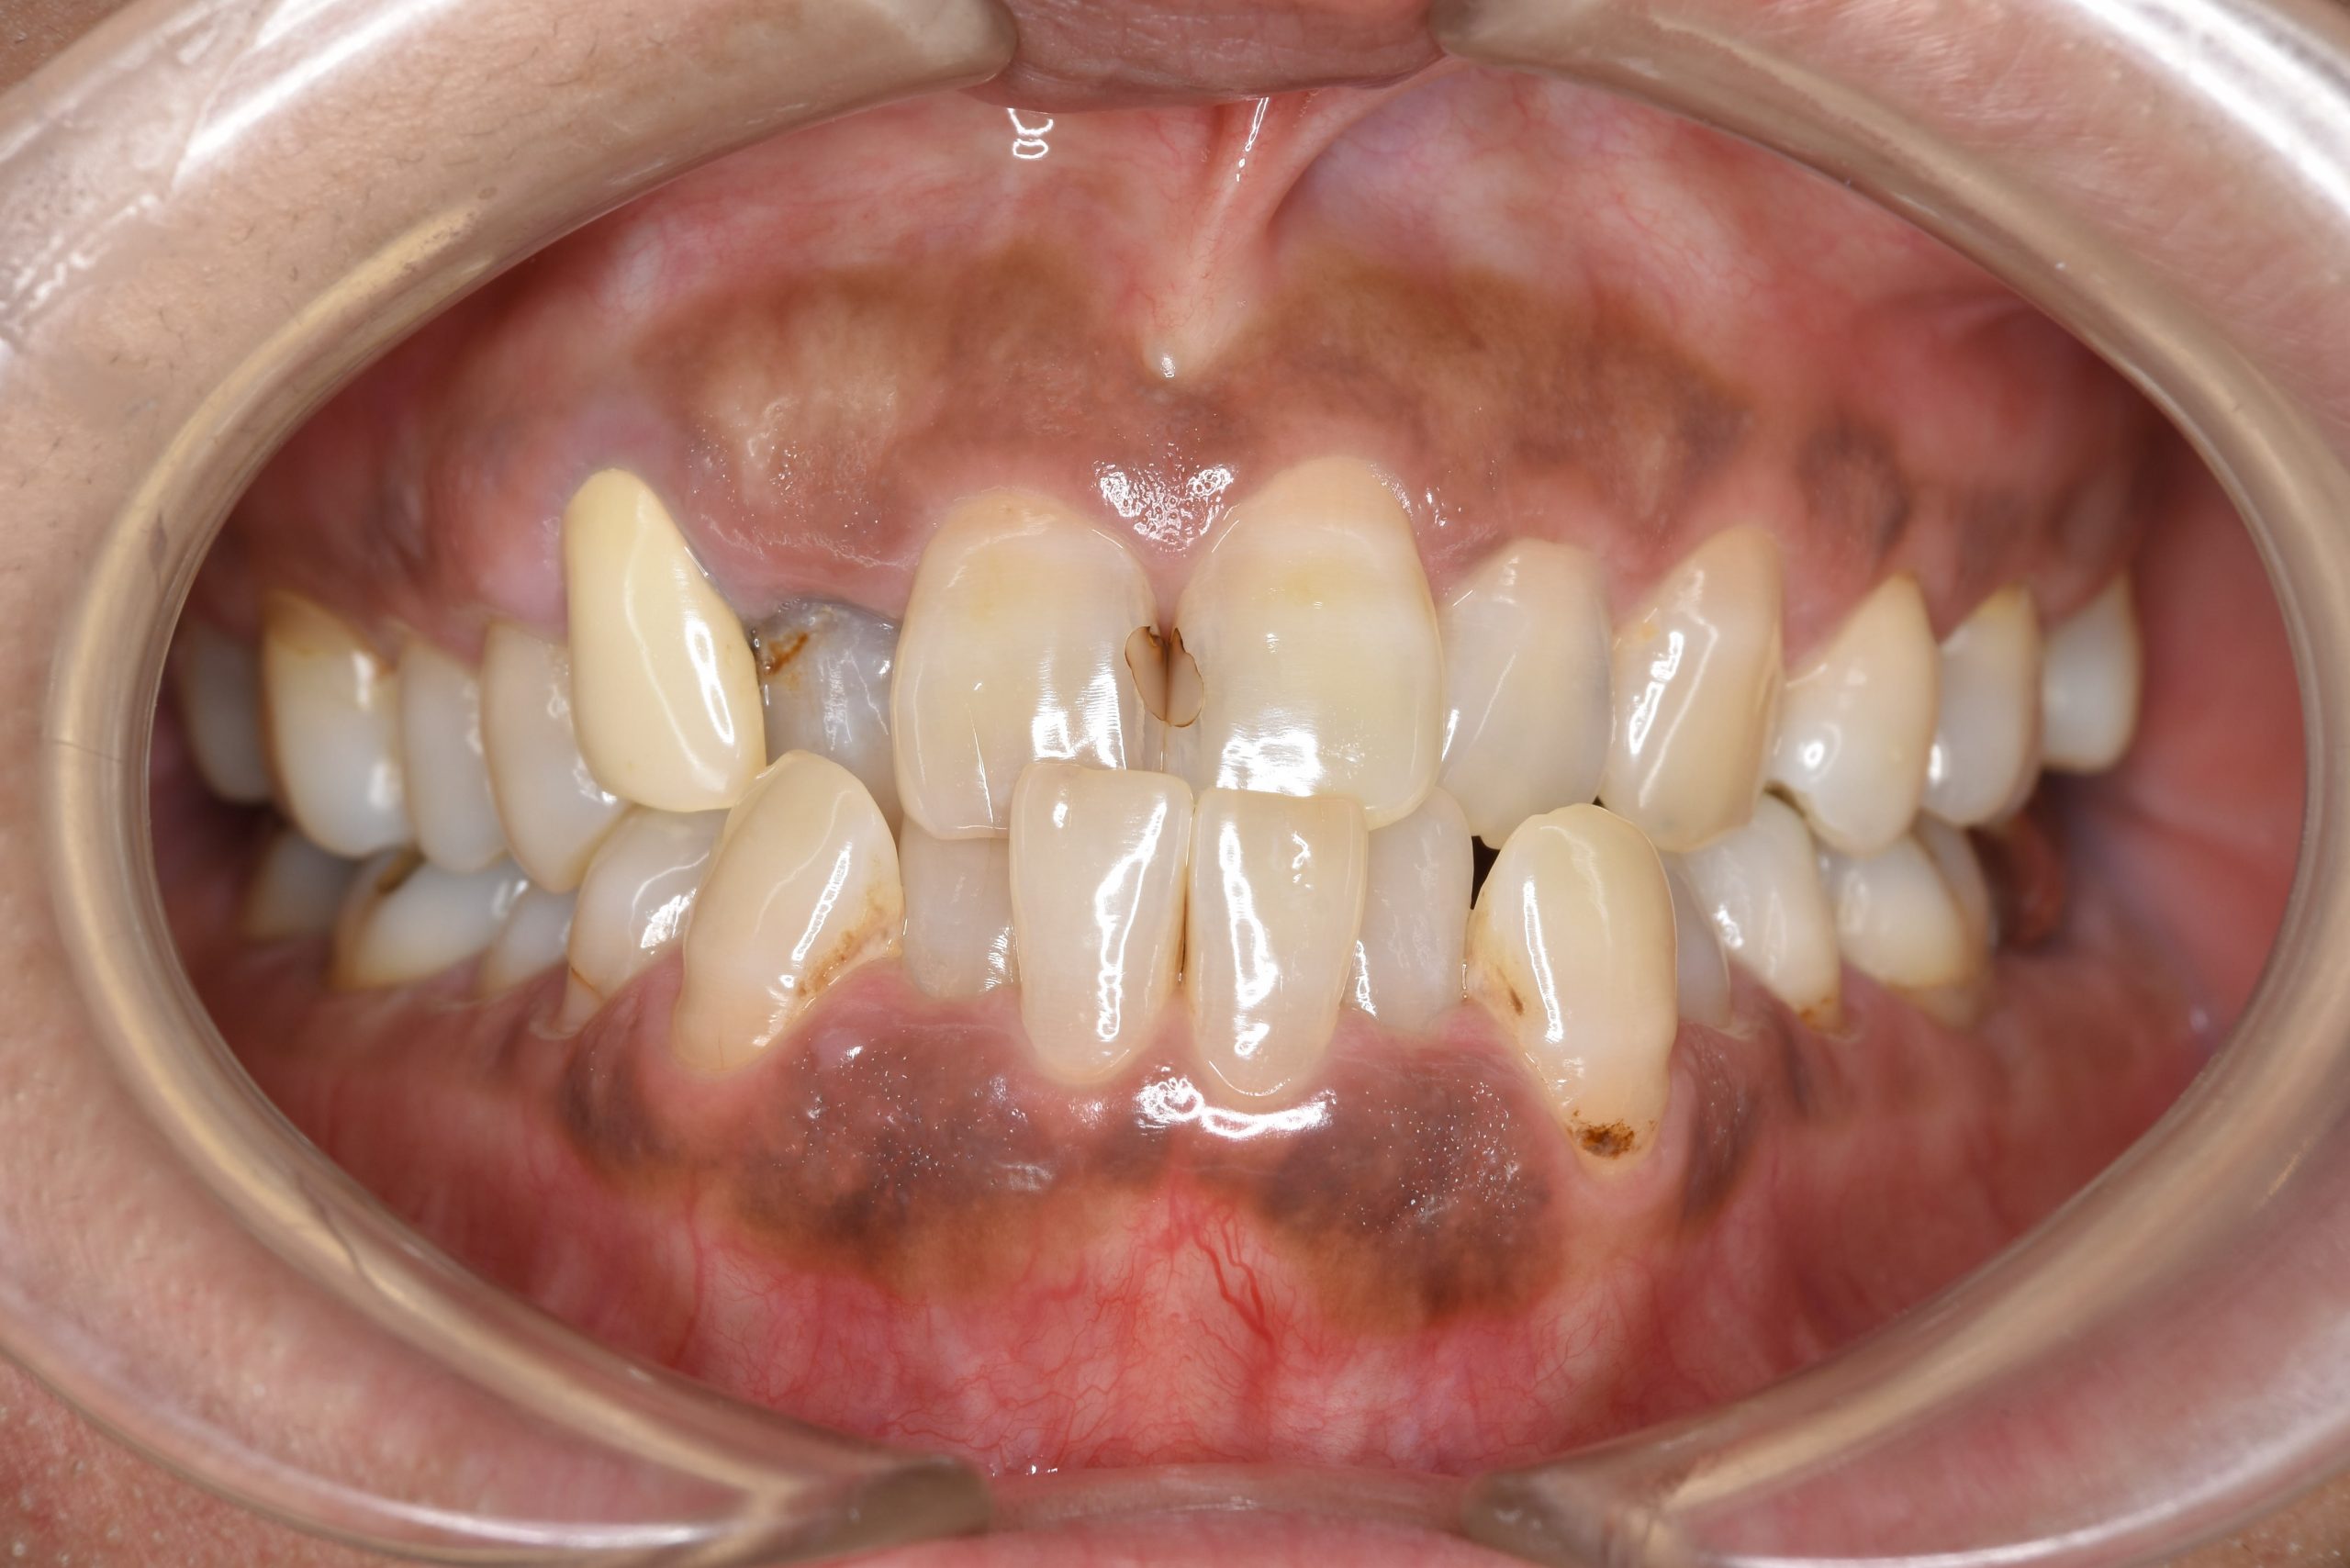

ビフォー

ワイヤー矯正治療|症例_588

主訴 かみ合わせ ※抜歯あり

施術内容 MSEと下顎リンガルアーチを用いて上下顎骨を拡大した。

その後下顎前歯を1本抜歯してマルチブラケット装置を用いて

歯牙を配列し良好な咬合を獲得した。側貌は改善した。